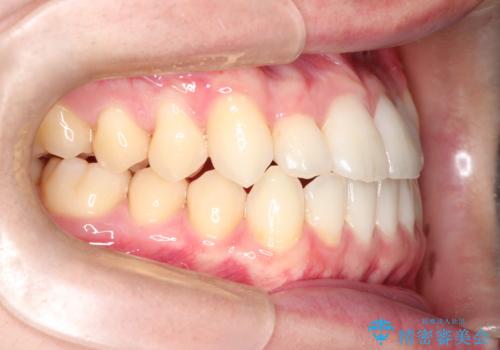

前歯のデコボコ インビザラインによる目立たない矯正

- 前歯のデコボコを主訴に来院された患者様です。

目立たないそうちをご希望されたので、インビザラインにて治療することとしました。

歯と歯の間をわずかに削ってスペースをつくり、デコボコを改善しました。